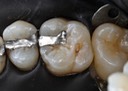

Joe Cha #20 prep